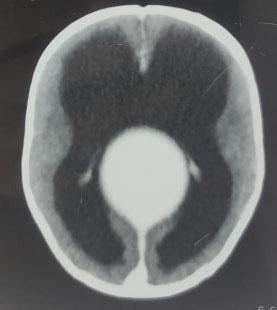

Fig 1 — A/C/O Close Fracture Supracondylar Humerus Left with Anterior Interosseous

CONCLUSION